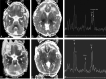

Background: Although the imaging, spectroscopic, and diffusion characteristics of brains of infants with neonatal encephalopathy have been described, the time course during which these changes evolve is not clear. The results of sequential MR imaging studies--including anatomic MR imaging, proton MR spectroscopy, and diffusion tensor imaging (DTI)--of 10 patients enrolled prospectively in a study of neonatal encephalopathy are reported to help to clarify the time course of changes in different brain regions during the first 2 weeks of life.

Methods: Ten neonates were prospectively enrolled in a study of the evolution of MR findings in neonatal encephalopathy and were studied 2 (8 patients) or 3 (2 patients) times within the first 2 weeks of life. The MR examination included spin-echo T1 and T2-weighted images, DTI, and long echo time (288 milliseconds) proton MR spectroscopy. Diffusion parameters (diffusivity [D(av)], fractional anisotropy [FA], and individual eigenvalues) were calculated for 10 1-cm2 regions of interest in each hemisphere that were placed based on anatomic landmarks. D(av) and FA were then measured manually in the same areas on a workstation. Metabolite ratios (NAA/Ch, Cr/Ch, Cr/NAA, Lac/Ch, and Lac/NAA) were calculated in 7 regions of interest. Imaging appearance, diffusion parameters, and metabolite ratios were then evaluated longitudinally (comparing with other studies on the same patient at different times) and cross-sectionally (comparing all studies performed on the same postnatal day).

Results: In most of the patients a characteristic evolution of DTI and MR spectroscopy parameters was seen during the first 2 weeks after birth. Although the anatomic images were normal or nearly normal on the first 2 days after birth in most patients, abnormalities were detected on DTI (both visually and by quantitative interrogation of D(av) maps) and proton MR spectroscopy (abnormal metabolite ratios). These parameters tended to worsen until about day 5 and then normalize, though in several patients abnormal metabolite ratios persisted. Of interest, as areas of abnormal diffusivity pseudonormalized within one region of the brain they would develop in other areas. Therefore, the pattern of injury looked very different when imaging was performed at different times during this evolution.